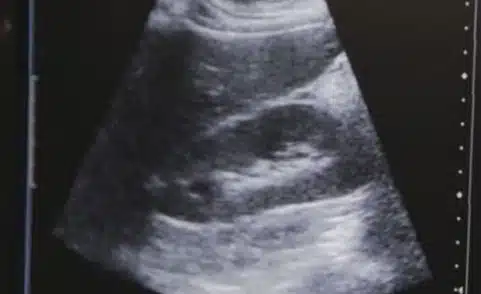

Your Aorta Is Important. Here’s How AAA Screening at RAYUS Radiology Can Ensure You’re Taking Care of It Posted In: Ultrasound